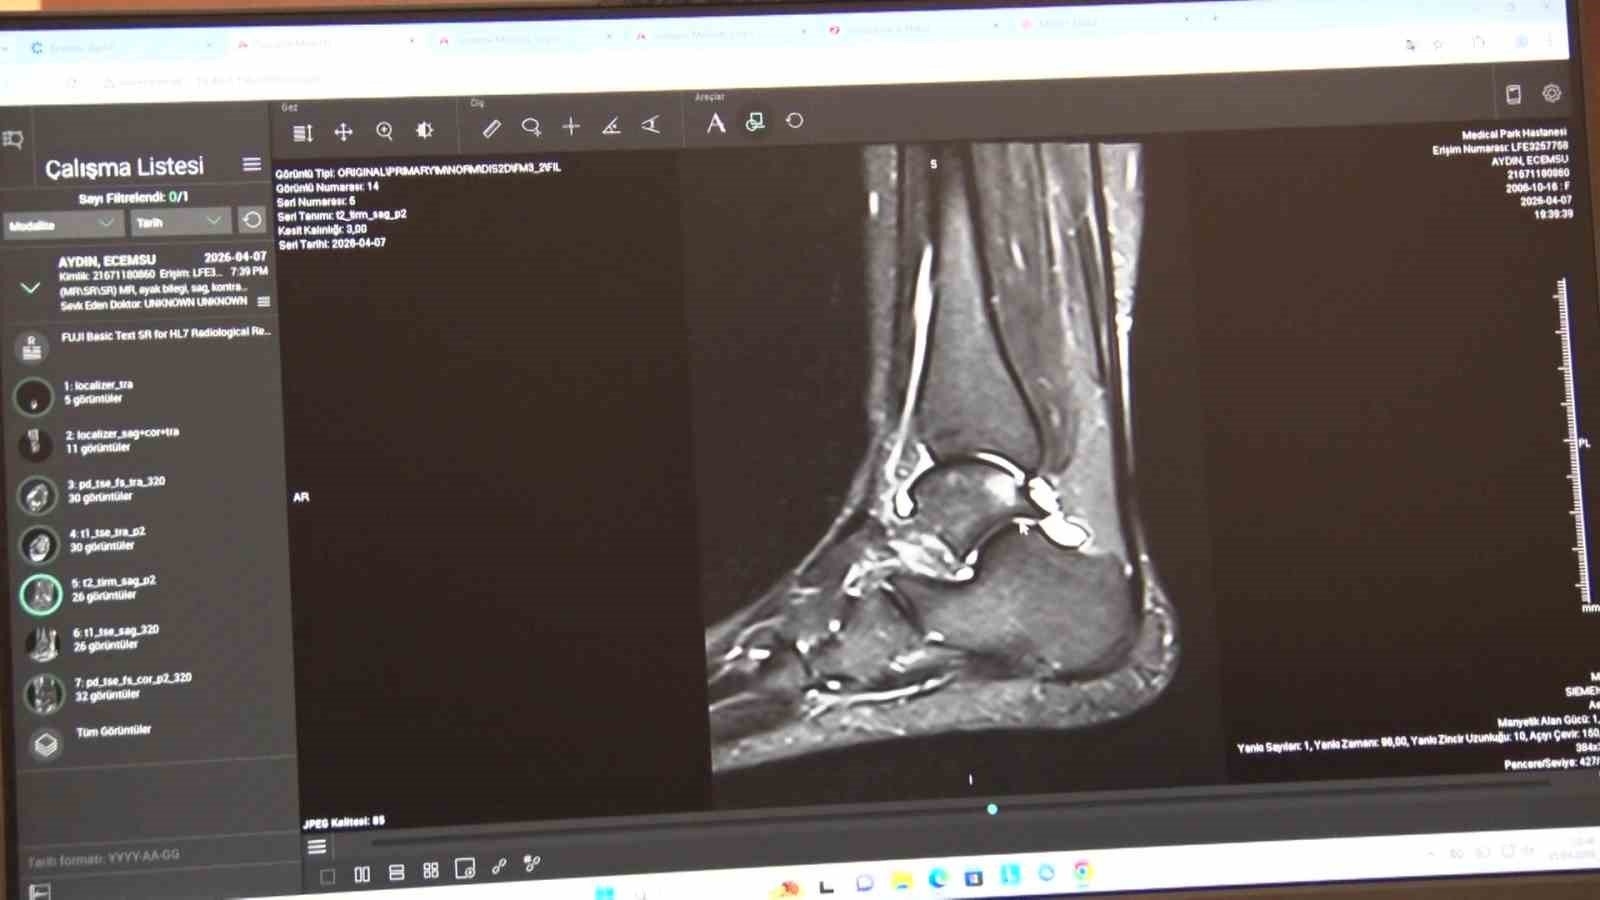

En sık görülen yaralanmalar diz ve tendonlarda